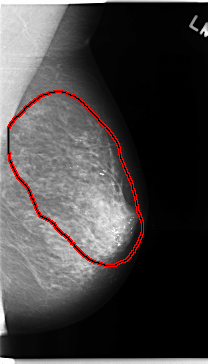

C_0144_1.LEFT_MLO

FILE: C_0144_1.LEFT_MLO.OVERLAY

TOTAL_ABNORMALITIES 1

ABNORMALITY 1

LESION_TYPE CALCIFICATION TYPE FINE_LINEAR_BRANCHING DISTRIBUTION REGIONAL

ASSESSMENT 5

SUBTLETY 5

PATHOLOGY MALIGNANT

TOTAL_OUTLINES 1

BOUNDARY